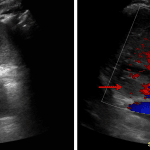

- Loss of the normal corticomedullary differentiation in the right kidney with an ill-defined hypoechoic region in the upper pole with peripheral, but no internal vascularity on Doppler analysis

Pyelonephritis with possible phlegmon/abscess

Loss of the normal corticomedullary differentiation in the right kidney, which in the context of clinical concern for urinary tract infection raises concern for pyelonephritis. An ill-defined hypoechoic region in the upper pole with peripheral, but no internal vascularity is concerning for possible phlegmon/developing abscess. Recommend followup ultrasound following treatment to ensure resolution.